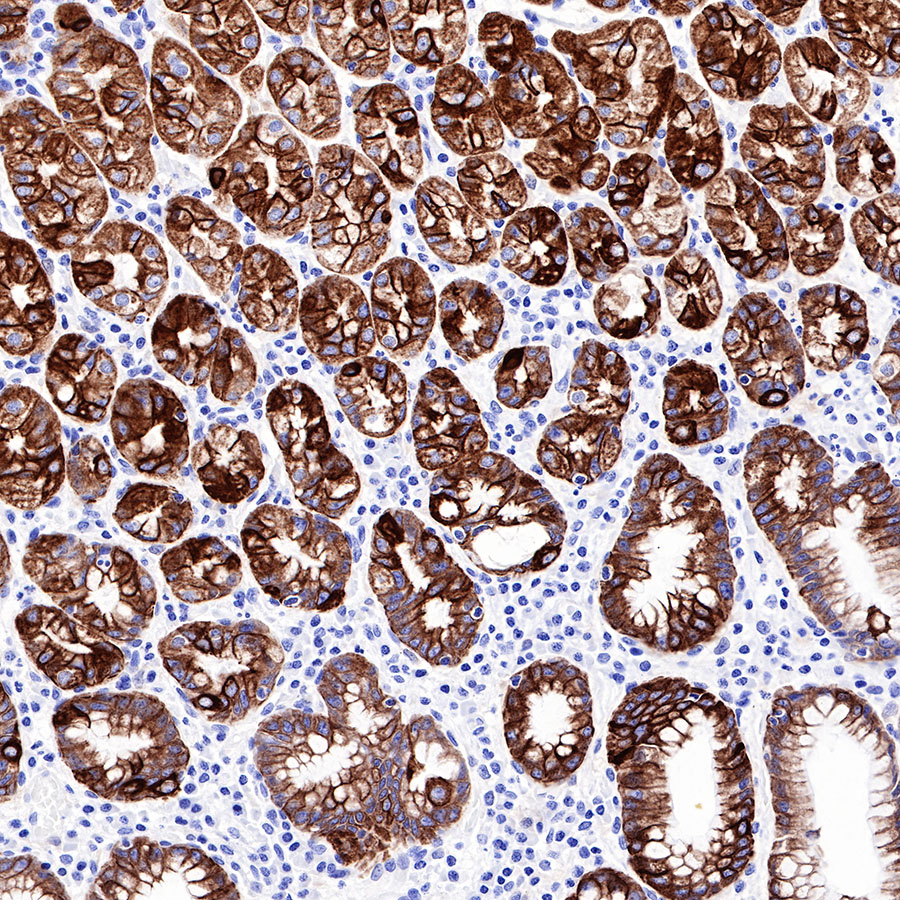

| IHC-P |

1:500-1:2000 |

Background

CK-LMW is low molecular weight cytokeratins and is expressed in monolayer or glandular epithelium of normal or tumor tissues, such as thyroid, breast, gastrointestinal or respiratory epithelium. It is expressed in adenocarcinoma and the vast majority of nonkeratinizing squamous cell carcinoma, but not in keratinizing squamous cell carcinoma. It combined with CK5/6 for diagnosis of adenocarcinoma and squamous carcinoma.